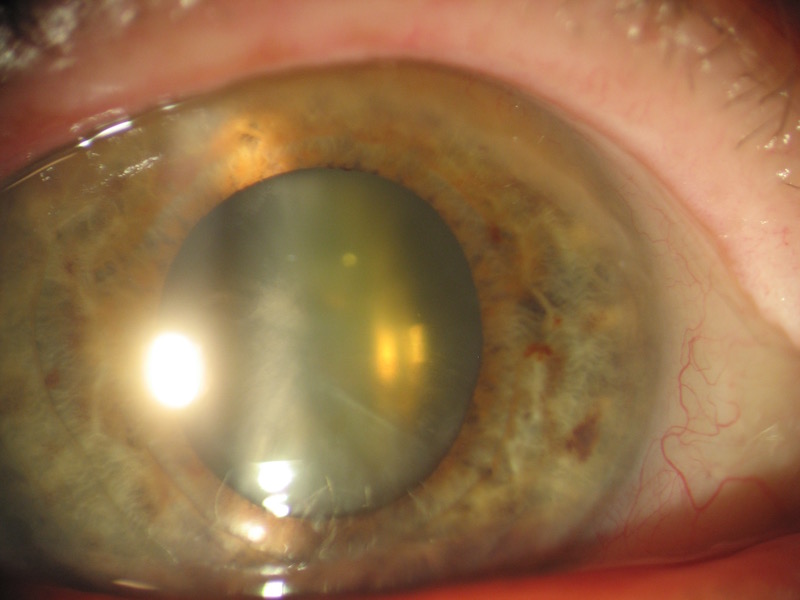

1) Cataract ++

Despite an important cataract with an invisible fundus of eye in Volk 90Δ or indirect ophthalmoscopy, Eidon manages to see the fundus of the eye.

- Cataract ++